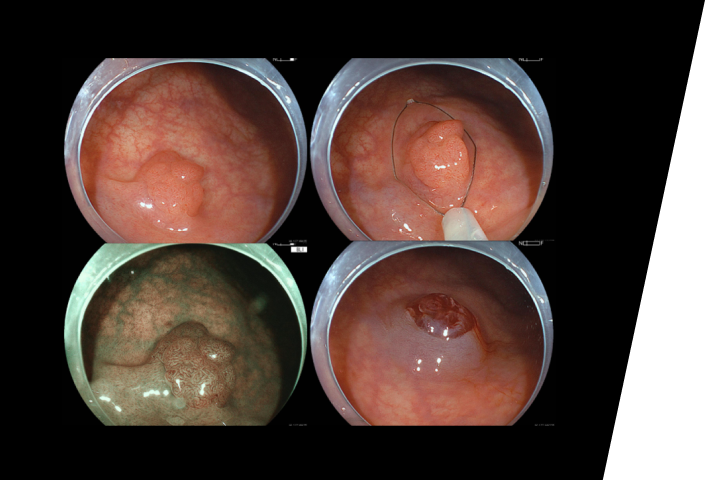

大腸カメラ(大腸内視鏡検査)は、直腸から盲腸までの大腸全体、小腸の一部までを観察する検査です。

大腸がんや大腸ポリープは、定期的な内視鏡検査を行っていれば、早期に発見でき、内視鏡での治療が可能な病気です。つまり、大腸がんは予防できる「癌(がん)」のひとつであると言えます。

FUJIFILM社の最新内視鏡システム(※)である「EP-8000」導入:画像品質の向上に伴い、病気を早期に発見できる機会が上昇することが期待されます。

一方で、病変を見落とする可能性がより低率になることに寄与すると考えられます。

当クリニックでは、大腸内視鏡検査でポリープが見つかった際、基本的にはその場でポリープを切除するため、入院は必要ございません(日帰りポリープ切除)。ただし、大きなポリープは癌が発生している可能性が高いため、紹介先の専門病院で入院治療を受けていただきます。

検査は肛門から内視鏡を挿入して、盲腸までの大腸と小腸の一部を直接観察します。検査時間は10-20分程度です(個人差があります)。

診察室にて実際の大腸カメラ画像をお見せしながら検査結果を医師より丁寧にご説明致します。また、ポリープ切除や組織検査を行った場合には、結果は後日判明いたしますため、その際には改めてご来院いただく必要がございます。